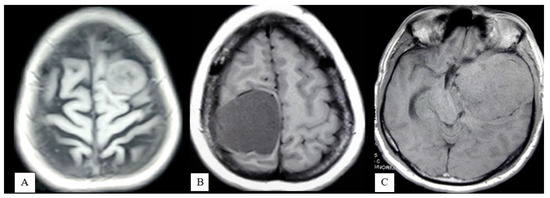

- Extrapial: Surgical cleavage plane lies outside the pia mater in more than two-thirds of the overall interface between tumor and cortex, regardless of whether an arachnoid membrane could be clearly identified (Figure 4A);

- Mixed: Cleavage plane lies outside the pia mater in more than one-third but less than two-thirds of overall interface (Figure 4B);

- Subpial: Tumor capsule exceeds the pia mater in more than two-thirds of the tumor cortex interface, and the surgeon was required to pass underneath the pia mater because of its incorporation into the tumor capsule (Figure 4C).